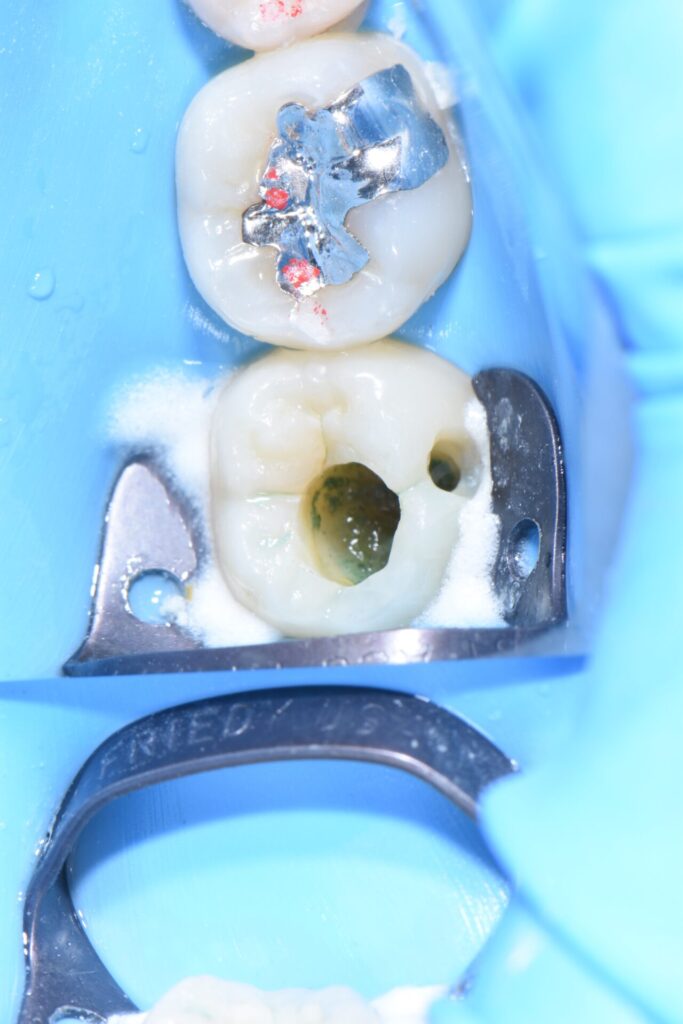

術後 通法に従い、ラバーダム防湿下でダイレクトボンディングにて修復治療